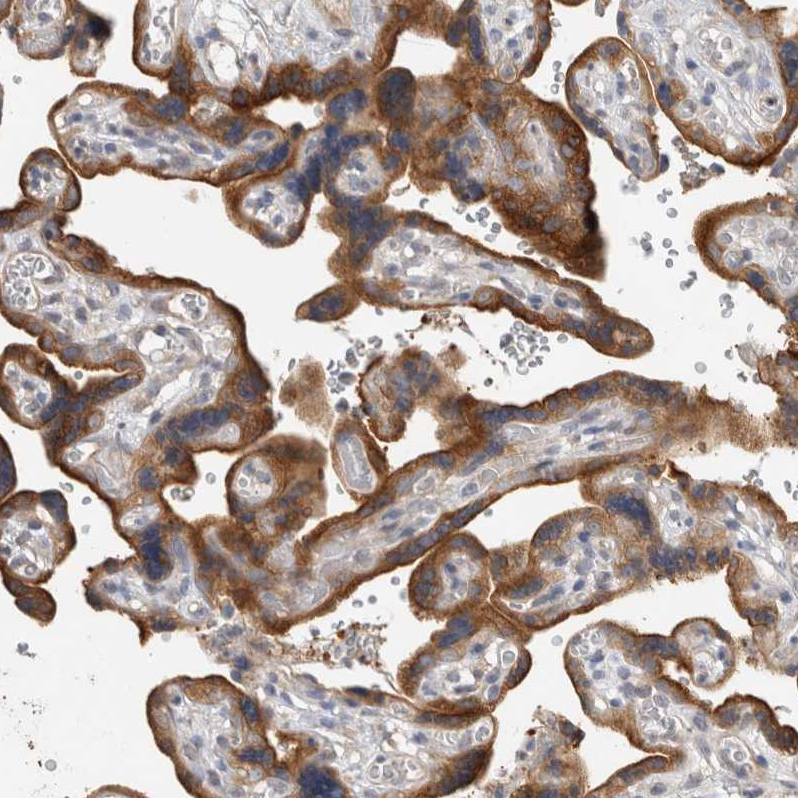

Immunohistochemical staining of human placenta shows moderate cytoplasmic positivity in trophoblastic cells.